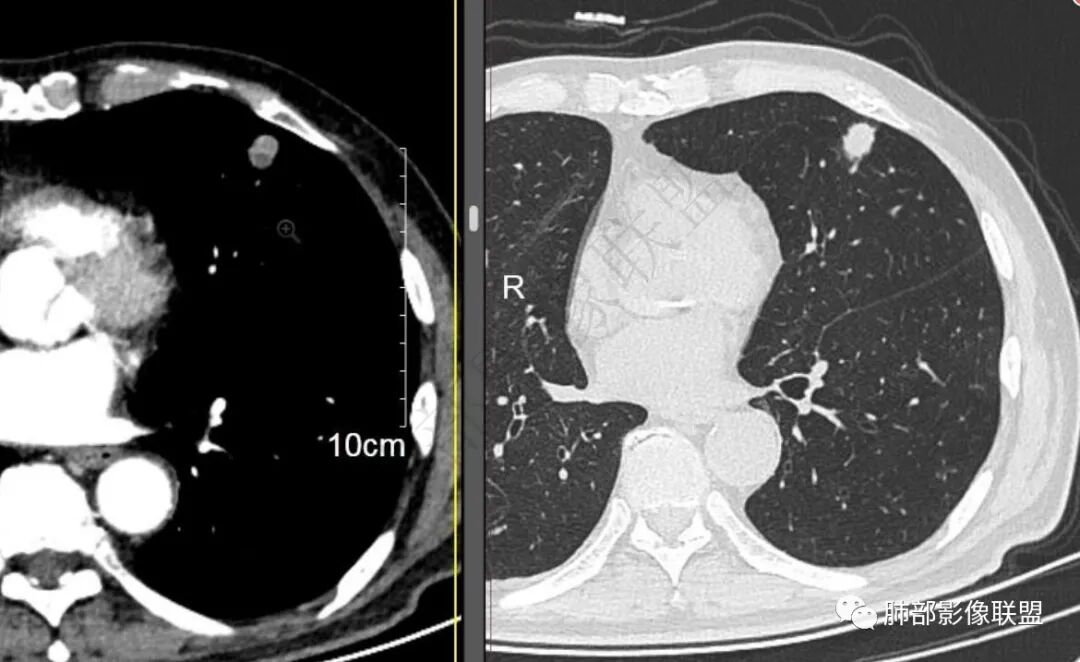

二..发现左肺上叶舌段实性密度小结节影,不规则略呈半环形,边界清楚,未见分叶、毛刺及磨玻璃晕。未见卫星病灶。

9个月后病灶明显增大,边缘较平直,部分膨隆,锁扣样外观,仍旧缺乏典型深分叶及张力,未见胸膜凹陷。

再1个多月后病灶继续增大,较明显不均匀强化,肺门一侧见低密度区。病灶边缘相对不清,可见毛刺。